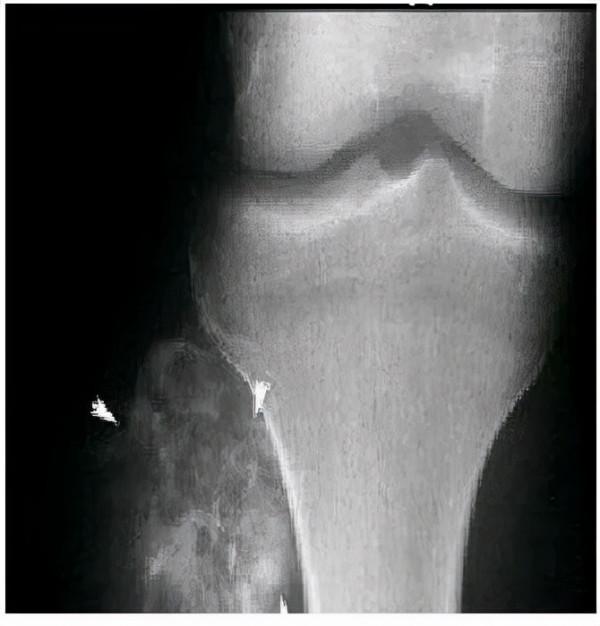

2、會出現骨和臨近關節的疼痛和腫脹,經常在夜間加重,疼痛嚴重程度與活動無關,疼痛的性質多種多樣,可為鈍痛、刺痛、牽拉痛等等

6、容易發生病理性骨折或變形,患者多出現無明顯誘因的一處或多處骨折,往往也是因此而就診的

3、骨腫瘤的疼痛集中在固定點,比如說膝關節,容易出現紅腫現象,但生長痛不會。總之,如果家裡孩子喊腿疼的話,家長一定別大意,要觀察孩子的具體症狀,免得延誤時機而不自知。實在不放心的話,最好去醫院做下檢查,由醫生進行診斷。